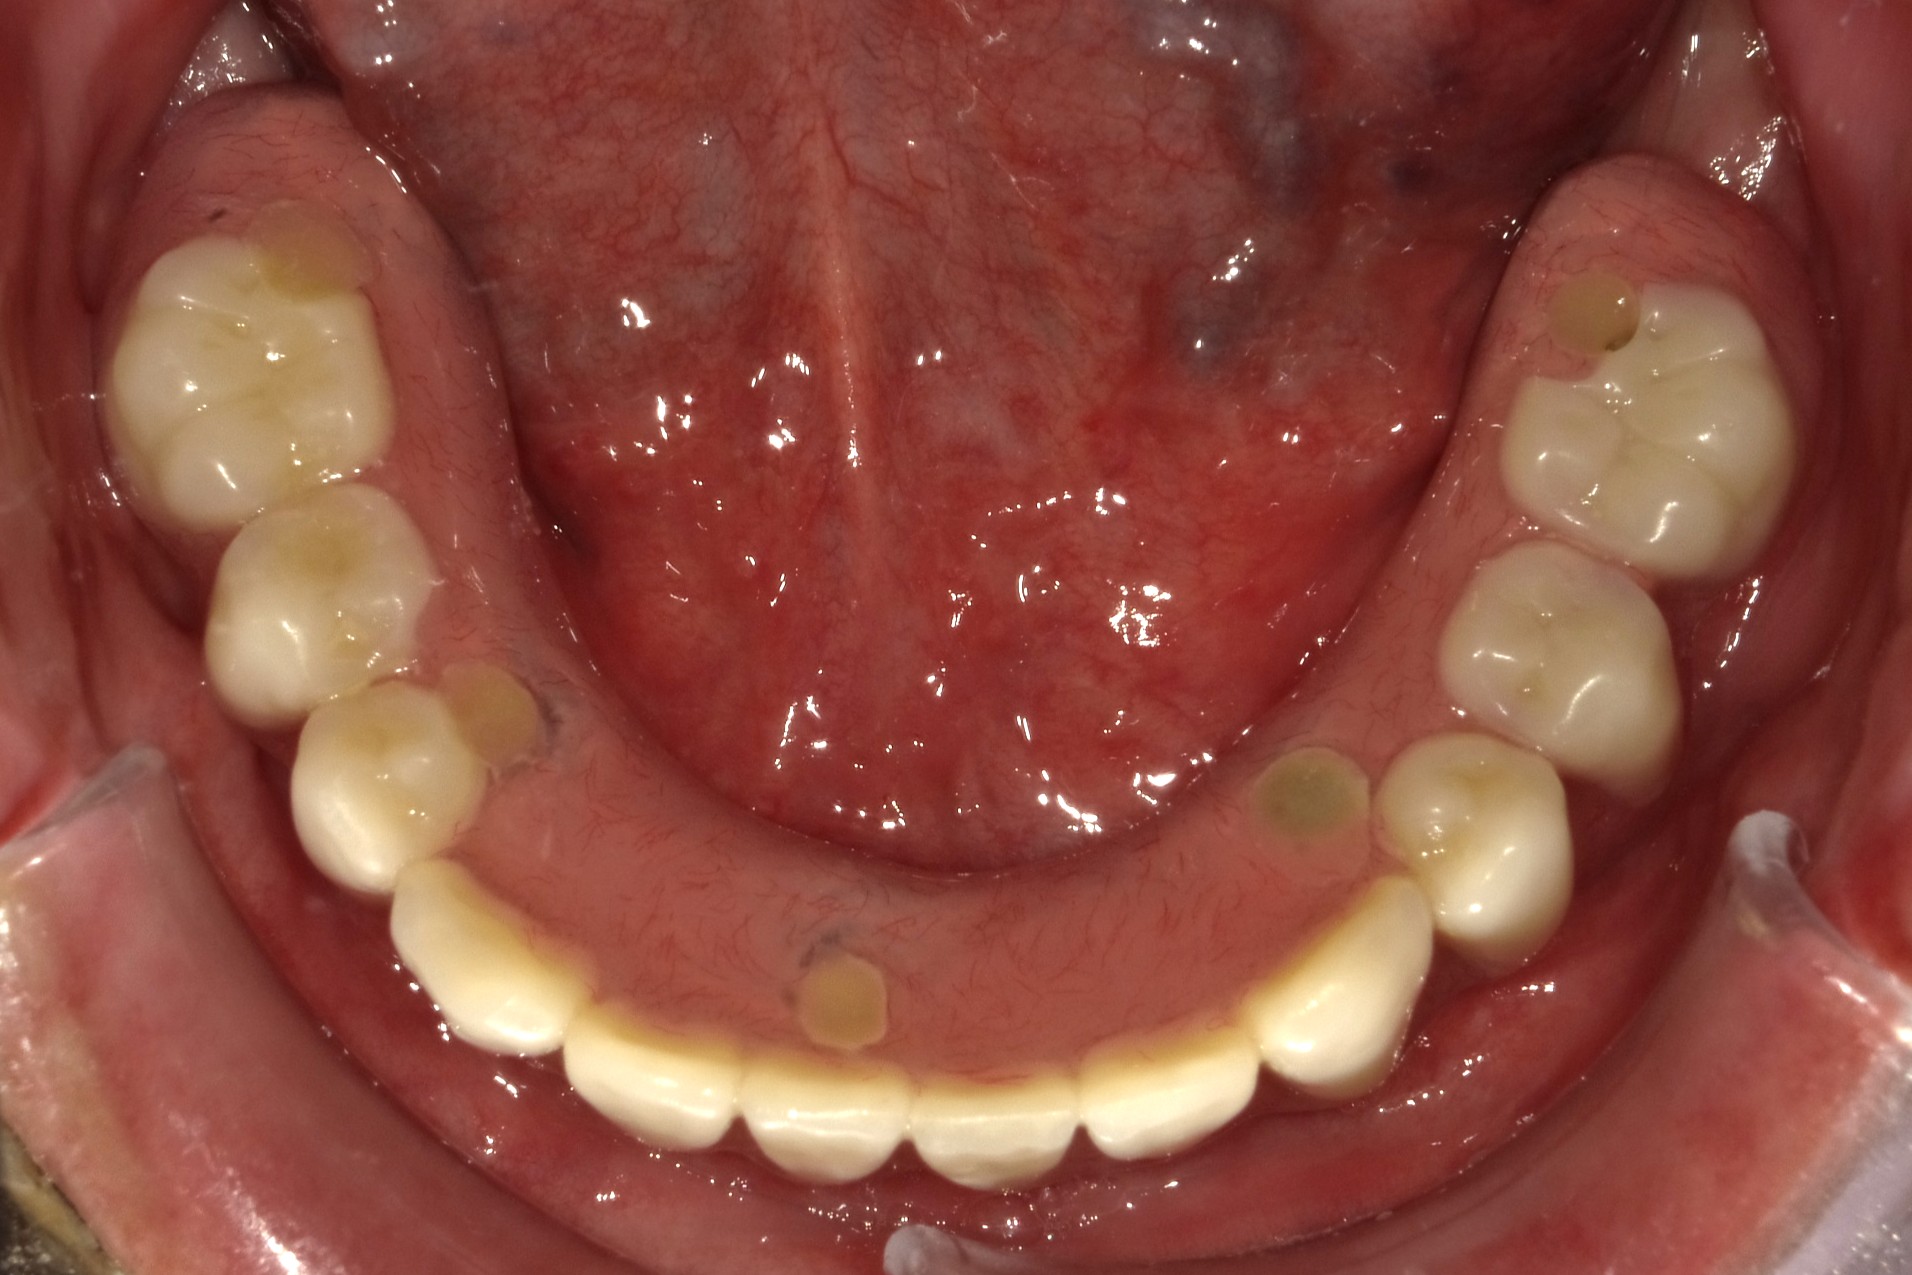

治療前

| 年齢・性別 | 60代・男性 |

| 主訴 | 入れ歯を作って使用していたが合わないので使用出来ない。ホームページで見たオールオン4を見てインプラントを何本か入れて繋げて欲しい。上も歯が無いが、まずは下から入れたい。 |

| 期間 | 8カ月 |

| 費用 | 2,473,900円 |

| 治療内容 | 下顎チタンインプラント5本(上部構造義歯タイプ) セデーション(静脈内鎮静法) ※インプラント治療の流れについてはインプラント専用ページを参照して下さい。 |